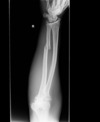

15

Q

Describe this fracture?

A

GALEAZZI

- Fracture of mid to distal radial shaft w/ dislocation of DRUJ; ligaments of inferior radioulnar joint ruptured, head of ulna displaced from ulnar notch of radius

- AIN injury

- Results from fall on outstretched hand, with wrist in extension & forearm forcibly pronated; inherently unstable, w/ tendency to redisplace after reduction